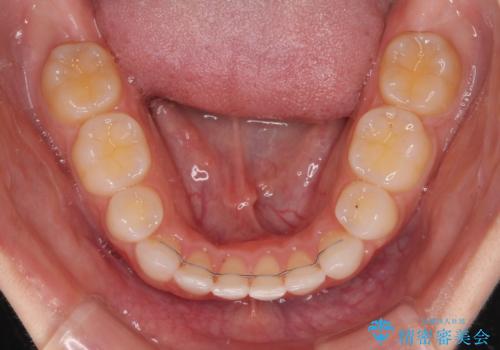

スペースを閉じるために期間を要しましたが、無事に綺麗な口元に仕上げることができました。

- 矯正治療後の保定が不十分だと後戻り(元の位置に戻ろうとする動き)をします